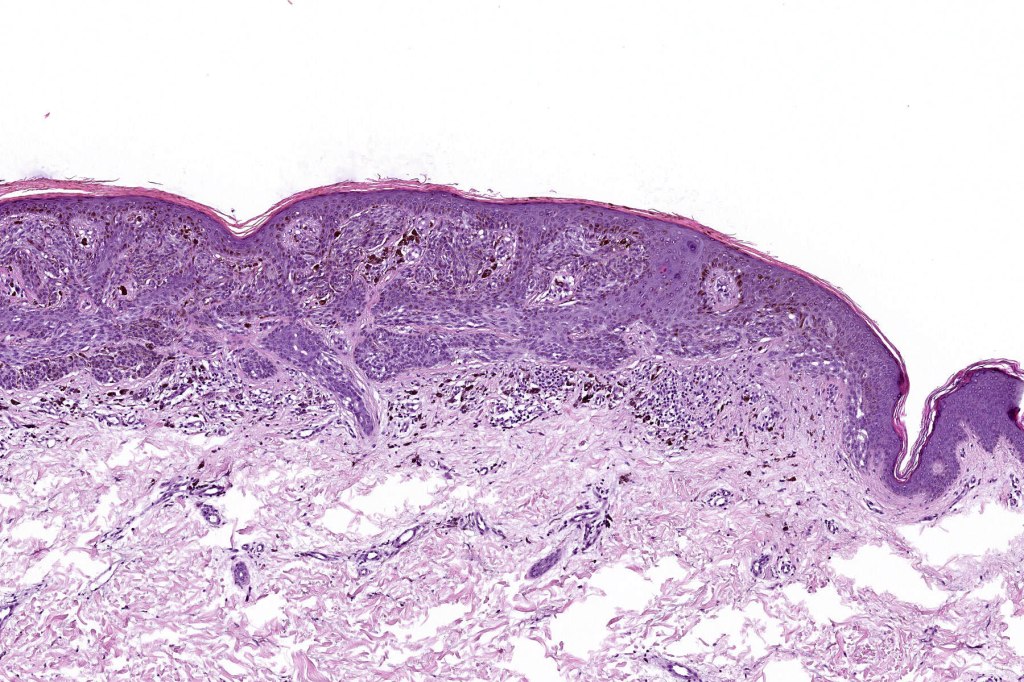

•Variant of Spitz nevus, readily identifiable at scanning magnification in the majority of cases

•Symmetrical and circumscribed with a characteristically flat lower border

•Vertically orientated oval junctional nests

•Junctional or compound

•Acanthosis & hyperkeratosis

•Maturation in compound variants

. Lymphocytic infiltrate often seen at base